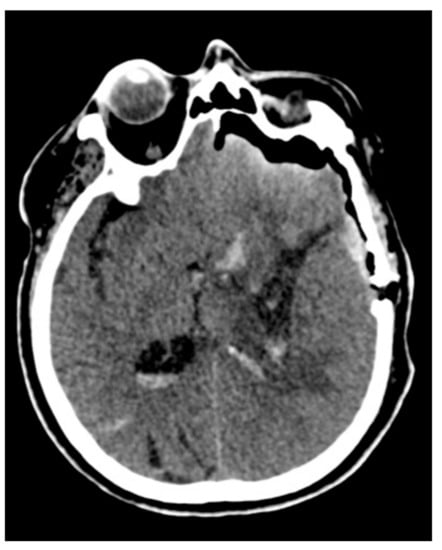

2.6. Surgical Management

Figure 2. The preoperative aspect of a deep-seated intracerebral hemorrhage (ICH).